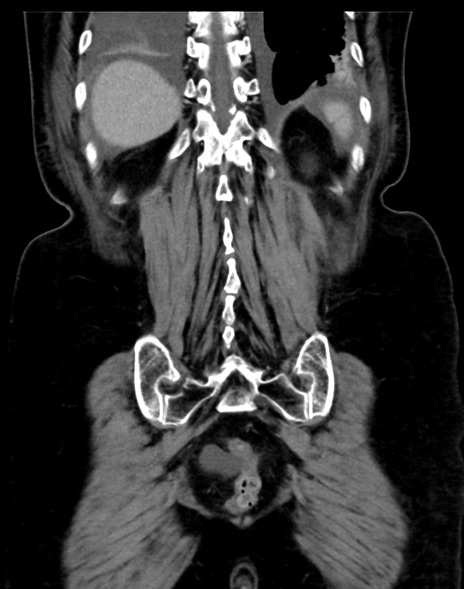

症例13 CT(冠状断像)1日半後